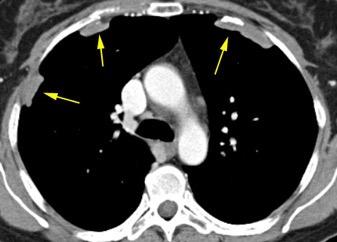

Derrame pleural 43-48% de pacientes con embolismo.

< 1/3 de hemitórax: 90%.(puede haber en lado opuesto).

Siempre exudados.

75% de los pacientes con TEP y derrame pleural tienen dolor pleurítico.

La disnea desproporcionada

Joroba de Hampton

Hallazgo muchas veces incidental.